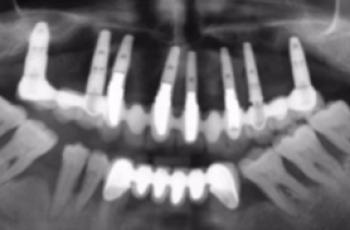

Tratamiento no quirúrgico de la periimplantitis. A propósito de un caso... Cirugía periodontal y periimplantaria | UIC Tratamiento no quirúrgico de la periimplantitis. A propósito de un caso... Se presenta el caso de una paciente de 58 años de edad, sin antecedentes médicos de interés y no fumadora. El motivo... Etiología, diagnóstico y tratamiento de la periimplantitis: Caso... Tto. Periimplantario | UV Etiología, diagnóstico y tratamiento de la periimplantitis: Caso... Presentamos nuevo caso clínico realizado por los doctores Manuel Rodríguez Aranda, Francisco... Efectividad del Tratamiento en Periodontitis Agresiva Tto. Periodontal | UIC Efectividad del Tratamiento en Periodontitis Agresiva El mantenimiento de la dentición natural en estado de salud ha sido un objetivo importante en... Injerto gingival libre alrededor de implantes dentales. A propósito de un... Cirugía periodontal y periimplantaria | UIC Injerto gingival libre alrededor de implantes dentales. A propósito de un... La cirugía mucogingival reconstructiva alrededor de implantes corrige los defectos de la... Terapia mucogingival en implantes: corrección de las secuelas mucosas de... Cirugía periodontal y periimplantaria | UV Terapia mucogingival en implantes: corrección de las secuelas mucosas de... El caso que se presenta a continuación muestra una resolución impecable de un defecto mucogingival... Importancia del mantenimiento en la evolución de un paciente con... Mantenimiento | UV Importancia del mantenimiento en la evolución de un paciente con... La periodontitis agresiva se define como una enfermedad de rápida progresión en la destrucción... Tratamiento de Recesiones Gingivales Clase III de Miller mediante técnica... Cirugía periodontal y periimplantaria | UIC Tratamiento de Recesiones Gingivales Clase III de Miller mediante técnica... El caso clínico que presentamos a continuación es el de una paciente que acude a la consulta... Tratamiento de un paciente con periodontitis crónica moderada generalizada Tto. Periodontal | UIC Tratamiento de un paciente con periodontitis crónica moderada generalizada El caso clínico que se presenta a continuación, muestra el tratamiento de una paciente...